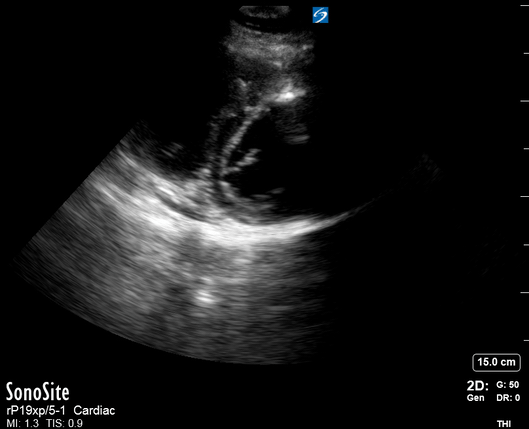

Effusion: is there a pericardial or pleural effusion?

Pericardial effusion is a continuum and can potentially evolve into haemodynamic collapse. Tamponade physiology is detectable earlier with ultrasound than with traditional physical examination, and it has been demonstrated that PoCUS improves mortality in penetrating cardiac trauma. Timely and accurate diagnosis is, therefore, vital.

THE VIEWS

The subxiphoid view is the most reliable for detecting pericardial effusion. Still, it is ideal to obtain different views not to miss a focal effusion as small amounts of fluid can lead to tamponade physiology. Tamponade does not link strictly to the size of the effusion, but correlates more with the speed of onset, causes, and haemodynamic effects.

PITFALLS & PLEURAL EFFUSIONS

A common error is to confuse a pericardial fat pad with effusion. Fatty tissue has a heterogeneous echotexture, moving in coordination with the myocardium, and it cannot be tracked around the heart, especially posteriorly and to the apex. Another pitfall is misinterpreting a pleural effusion as a pericardial effusion. However, they can be differentiated by their relationship to the descending aorta. Pericardial effusion may be seen between the aorta and the LV free wall, whereas pleural effusions are posterior to the descending aorta. Lastly, other causes, namely hypovolaemia and large pleural effusions, can cause RA and RV collapse.

CARDIAC TAMPONADE

Progressively rising pressure translates into evolving tamponade, and this accompanies a series of ultrasound findings:

Initially, the RA collapses during ventricular systole (closed AV valves).

Followed by RV collapse in ventricular diastole (open AV valves).

Ultimately leading to LV collapse.

In addition, the presence of a non-collapsible, plethoric IVC is one of the most sensitive signs of tamponade, and a finding easy to visualise. Conversely, a pericardial effusion in a haemodynamically stable patient with a collapsible IVC is unlikely to represent tamponade.

Chamber collapse can be assessed in M-mode, where the collapsing RV is seen as a notch that takes place right after the mitral valve opening and before its closure (during diastole).

M-mode is used to demonstrate RV collapse (arrow) occurring right after mitral valve opening during diastole. (star = pericardial effusion, 1. RV free wall, 2. Interventricular septum, 3. mitral valve, 4. LV free wall). From: The "5Es" of emergency physician-performed focused cardiac ultrasound (11).